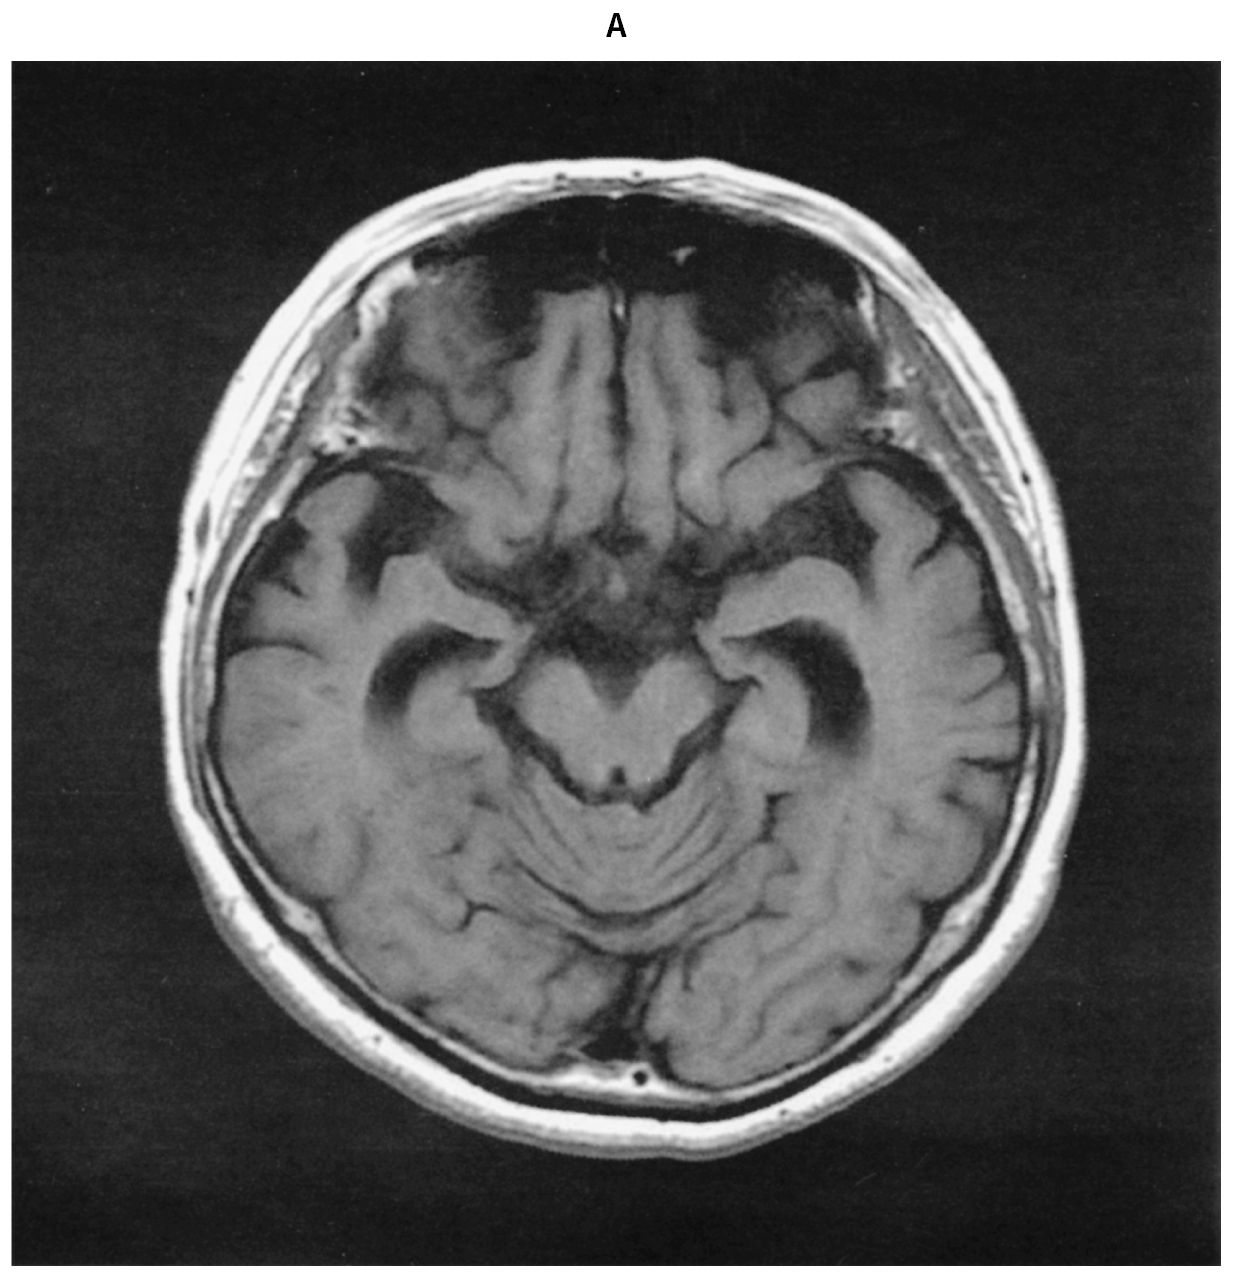

83歳の男性。自分の持ち物を盗られると訴えるようになり,対応に困った家族に連れられ受診した。1年前から物忘れが目立つようになった。次第に意欲が低下し,散歩に行かずに寝ていることが多くなった。2か月前から金銭に対する執着が強くなり,預金通帳や印鑑をしまい忘れては誰かに盗まれたと訴えるようになった。既往歴と家族歴に特記すべきことはない。意識は清明。脳神経,四肢の運動と感覚に異常を認めない。Mini-Mental State Examination 〈MMSE〉18点(30点満点)。血液生化学所見に異常を認めない。頭部単純MRIのT1強調像(A)と脳血流SPECT(B)とを下に示す。